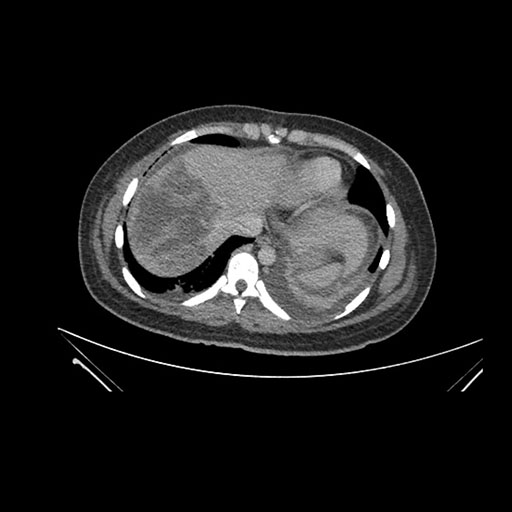

Axial Arterial

Axial Venous